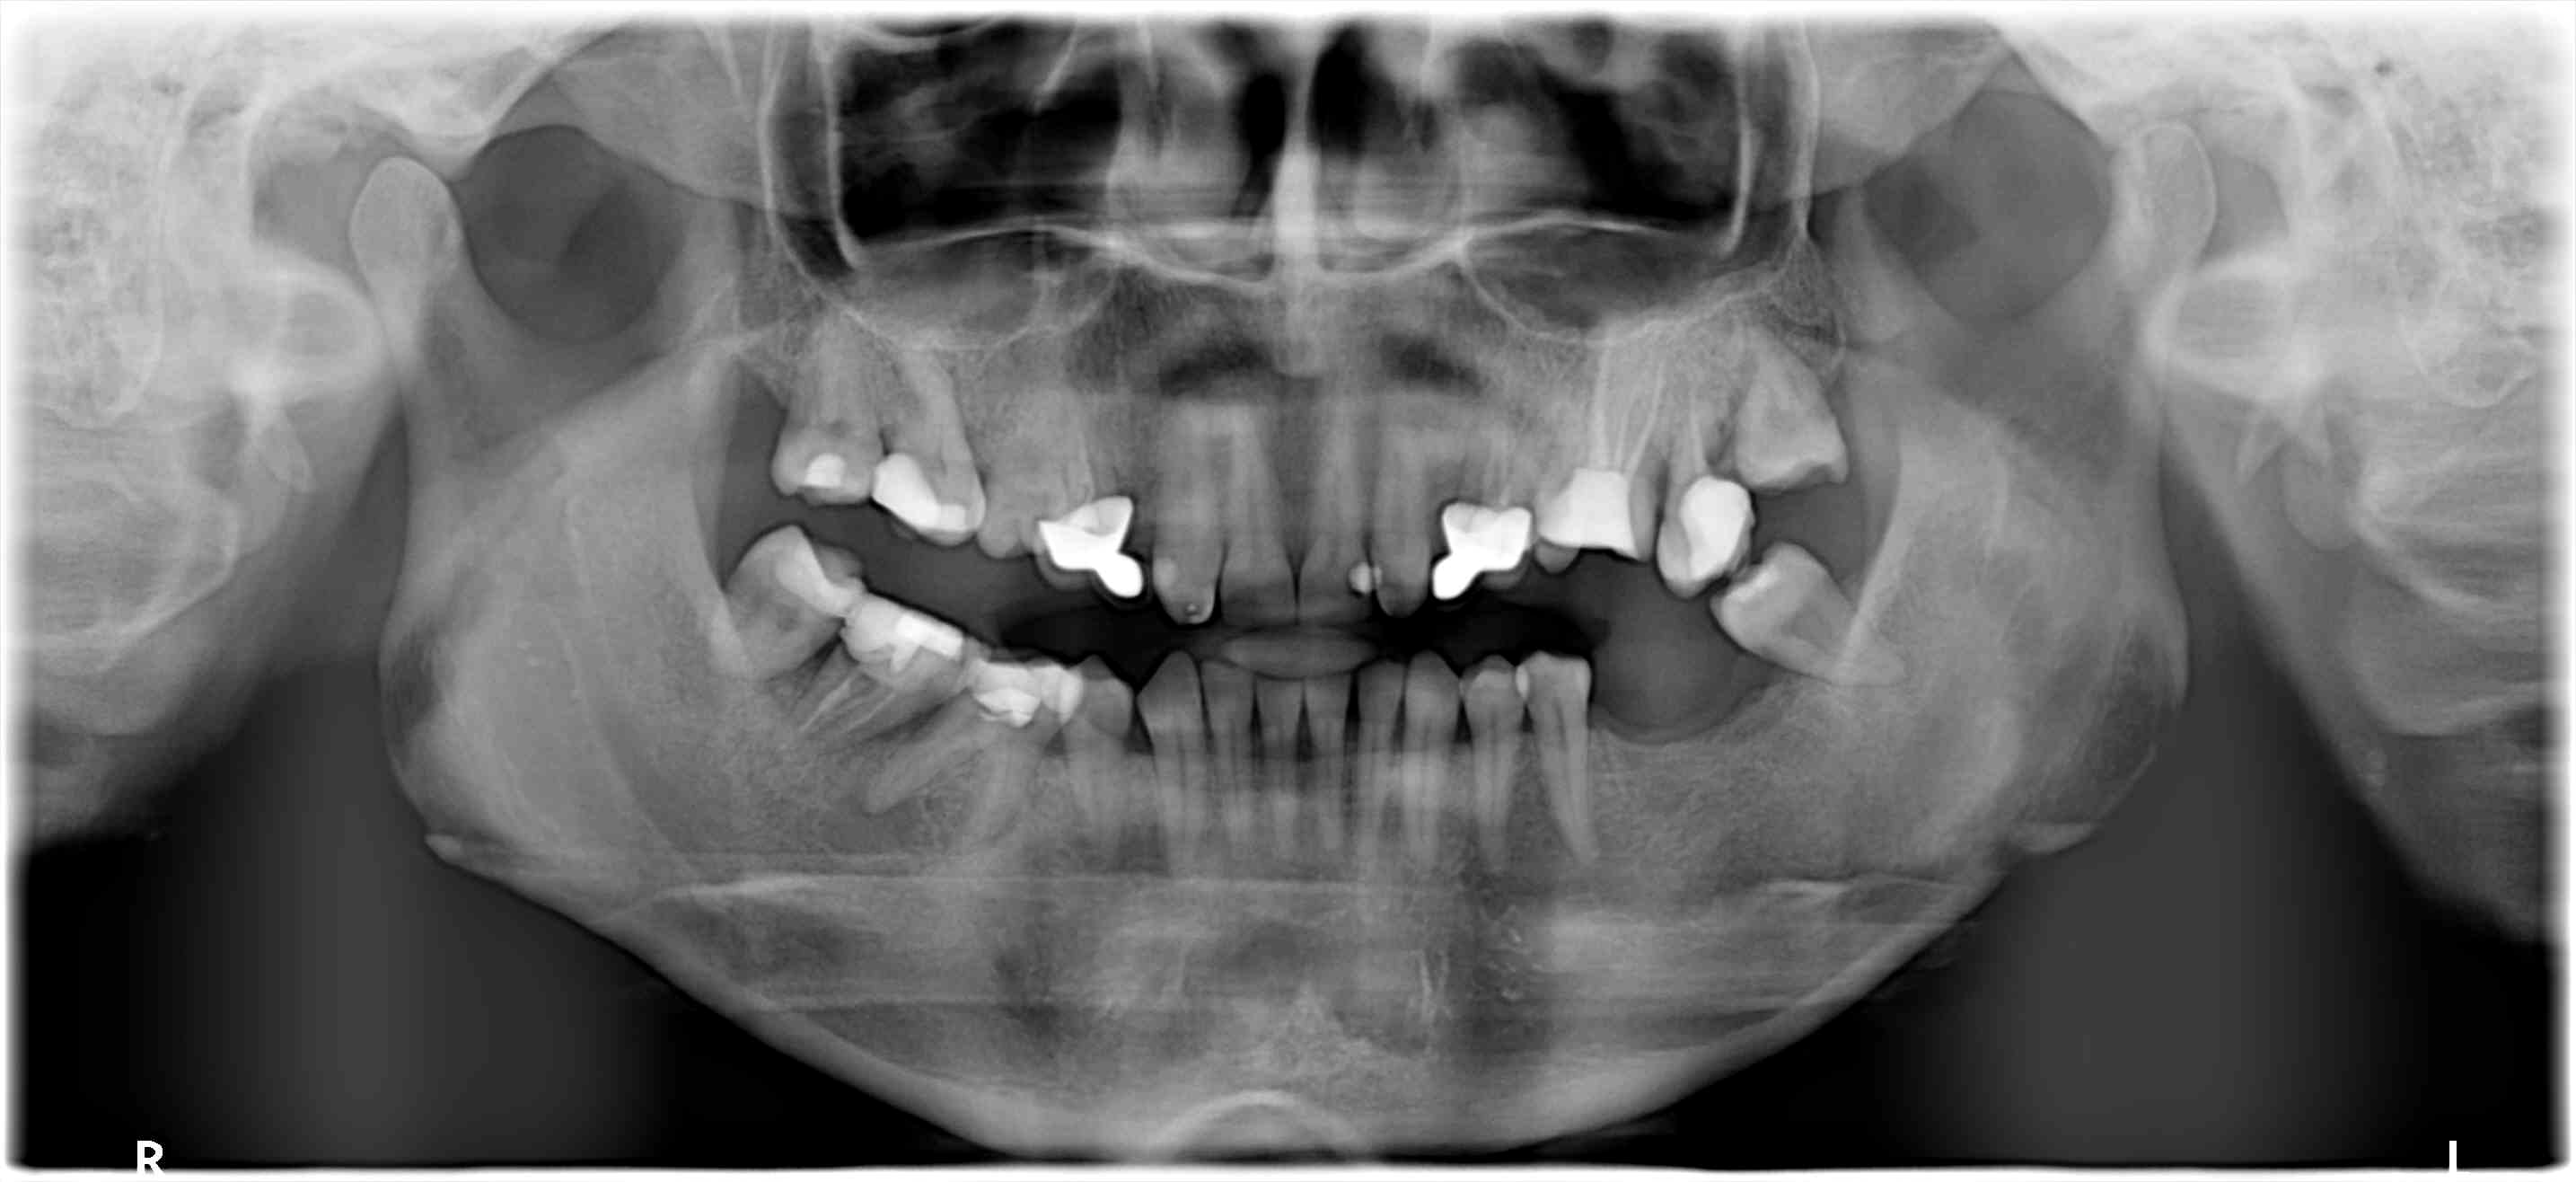

Pano du cas...

Vu la pano c'est pas vraiment de la mci qui est possible...

Ça va être soit long et compliqué soit bâclé...

Dans tous les cas vu l'état d'esprit du mari vaut peut être mieux que ce soit pas toi qui gère...

Pi faut pas désespérer.... T'auras peut être un beau cas de dépose et de réhabilitation correcte à faire d'ici quelques temps....